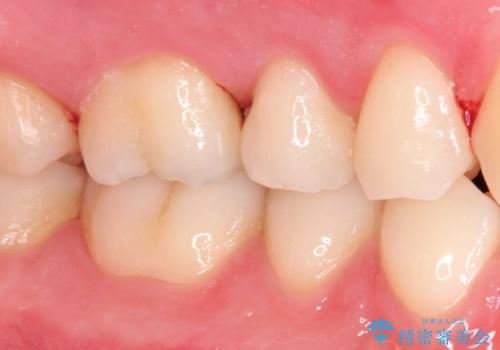

【セラミックインレー】定期検診にて虫歯を発見

- 定期検診にて虫歯を発見したため、セラミッククラウン、セラミックインレーにて治療を行いました。

小臼歯の虫歯は歯髄に近かったため、部分的断髄法にて歯髄を部分的に保存した治療をおこなっています。